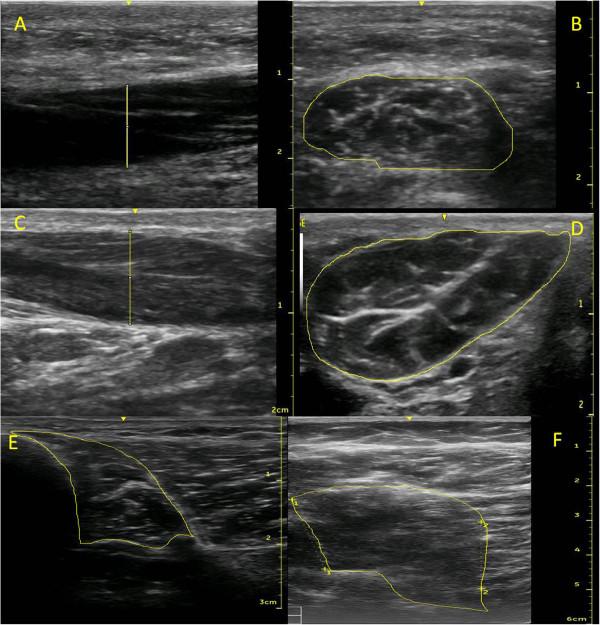

The abductor hallucis, flexor hallucis brevis, flexor digitorum brevis, quadratus plantae and abductor digiti minimi muscles in the foot, and the flexor digitorum longus and flexor hallucis longus muscles in the shank were assessed in five males and five females (mean age = 32.1 ± 10.1 years). Muscles were imaged using a GE Venue 40 ultrasound (6-9 or 7.6-10.7 MHz transducer) in a random order, and on two occasions 1-6 days apart. Muscle thickness and cross-sectional area were measured using Image J software with the assessor blinded to muscle and day of scan. Intraclass correlation coefficients (ICC) and limits of agreement were calculated to assess day-to-day repeatability of the measurements.

The method was found to have good reliability (ICC = 0.89-0.99) with limits of agreement between 8-28% of the relative muscle size.